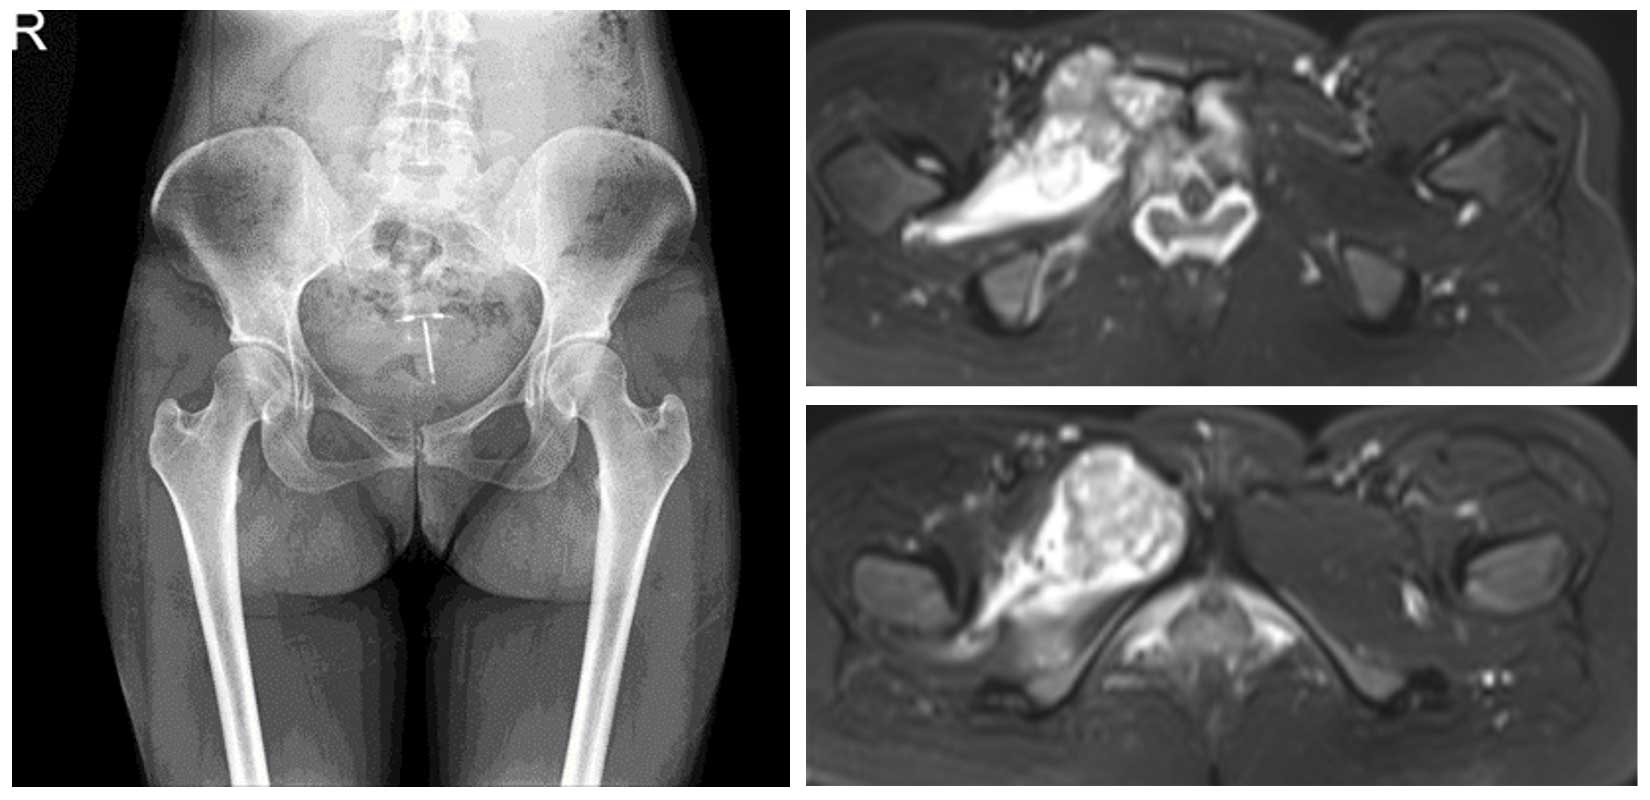

Ameliyat Öncesi: Röntgende sağ pubik kolda düzensizlik, MR’da eşlik eden yumuşak doku komponenti ve peritümöral ödem görülmekte.